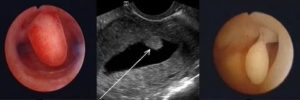

По внешнему виду железисто-фиброзный полип имеет вид образования розового или бордового цвета, расположенного в матке. Оно состоит из тела и ножки с кровеносными сосудами. Полип может иметь разнообразную форму: округлую, грибовидную, на тоненькой ножке, на широком основании.

Эндометриоидные полипы обычно обнаруживают во время проведения профилактического гинекологического осмотра с помощью зеркал. Также в диагностике полипов требуется проведение УЗИ органов малого таза.

Врачи констатируют утолщение слоя эндометрия, разрастание слизистой оболочки, расширение полости матки. Но полипы с железистой структурой не всегда заметны на УЗИ, поскольку по своему внешнему виду напоминают эндометрий. Также сложно отличить полип и миому во время этого обследования.

Гистероскопия матки дает возможность уточнить диагноз и повышает достоверность диагностики до 97%. Эта методика позволяет увидеть всю маточную полость и имеющиеся в ней образования. При гистероскопии требуется общий наркоз, так как матка обследуется с помощью гистероскопа, а после него происходит удаление образования.

Наросты обладают небольшим размером (но могут сильно разрастаться). Это гладкая субстанция розового цвета. Имеет строму и тело. Располагается на тонкой ножке или на широком основании.Второй тип больше склонен к малигнизации. В ножке много кровеносных сосудов, снабжающих его для роста. Полипы с железисто-фиброзной структурой бывают единичными и множественными.

- Кольпоскопии. Благодаря визуализации обнаруживаются любые отклонения в эндометрии.

- Гистероскопии. Самый информативный метод. Процедуру проводят зачастую в комплексе с выскабливанием. В ходе изучения полипа делают биопсию.